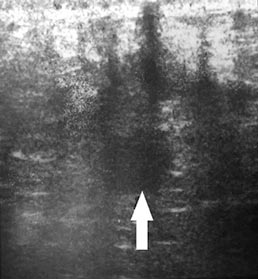

Наглядно ультразвуковая картина послеоперационных ран представлена на рис. 1–5. Показана положительная динамика разрешения полостных образований послеоперационной раны на 3-и, 5-е и 7-е сутки. Переход гипоэхогенной зоны в сторону уменьшения и появления участков гиперэхогенной структуры на 7-е сутки послеоперационного периода свидетельствует об уменьшении воспалительных процессов, снижении риска увеличения полостных образований и формировании фазы регенерации.

Рис. 1. Ультразвуковая картина передней брюшной стенки живота пациента К. 42 лет на 3-и сутки после лапаротомии. Определяется гипоэхогенная зона шириной 12,5 мм в области апоневроза белой линии живота